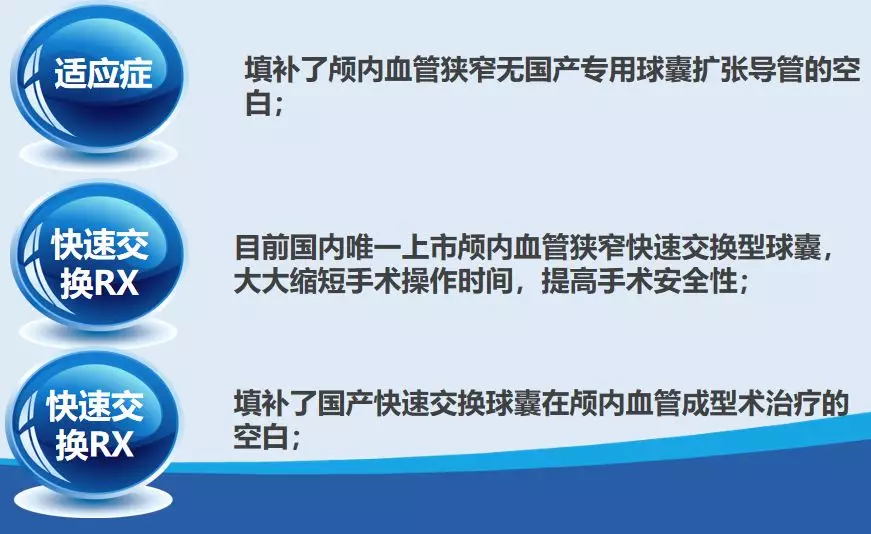

赛诺 2.0*15mm球囊扩张

赛诺 2.0*15mm球囊扩张